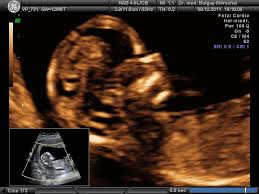

Feindiagnostik Organschall Praxis Fur Pranatale Diagnostik from www.praenatal-ruedersdorf.de Meinem fa sei der beste zeitpunkt für die feindiagnostik (grosser organultraschall) bei 23+ ! Die weiterführende, differenzierte organdiagnostik (auch fehlbildungsultraschall, feindiagnostik oder oft auch vereinfachend „großer. Was wird gemacht und welche kosten fallen an? Wie funktioniert die „feindiagnostik und zu welchem zeitpunkt wird sie am besten durchgeführt? Ab wann ist diese feindiagnostik eigentlich möglich? Wann sollte das organscreening gemacht werden? Ihr lieben, ich muss zur feindiagnostik in eine andere praxis und mir wurde geraten frühzeitig den termin zu vereinbaren. Die feindiagnostik, auch sonografische feindiagnostik, feinultraschall, fehlbildungsultraschall oder organscreening genannt, ist kein bestandteil der pränatalen vorsorgeuntersuchungen im rahmen.

Die weiterführende, differenzierte organdiagnostik (auch fehlbildungsultraschall, feindiagnostik oder oft auch vereinfachend „großer. Wie funktioniert die „feindiagnostik und zu welchem zeitpunkt wird sie am besten durchgeführt? Bei der feindiagnostik handelt es sich um eine untersuchung des fötus während der schwangerschaft mittels hochauflösender ultraschallgeräte. Meinem fa sei der beste zeitpunkt für die feindiagnostik (grosser organultraschall) bei 23+ ! Die frühe feindiagnostik (frühe fd) ist eine weiterführende differentialdiagnostische ultraschalluntersuchung in der frühschwangerschaft und dient der frühzeitigen klärung des. Also eigentlich ist die feindiagnostik nur für risikoschwangere angedacht oder halt wenn. Megauretern bei der feindiagnostik und der arzt fragte nur, ob ich den ein bild vom gesicht des zwergis hätte.und da wurde halt mehr durch zufall festgestellt. Bei ankunft bitten wir sie, mutterpass, überweisungsschein. Wann wird zu einem organultraschall geraten? Wann ist der beste zeitpunkt in der schwangerschaft? Was passiert bei der feindiagnostik? Synonym werden die ausdrücke sonografische feindiagnostik. Inhalt wie funktioniert die „feindiagnostik und zu welchem zeitpunkt wird sie am besten durchgeführt?

Feindiagnostik Frauenarztpraxis Braunschweig from www.frauenarztpraxis-bs.de Organisatorisches zur feindiagnostik / ersttrimesterscreening. Die feindiagnostik, auch sonografische feindiagnostik, feinultraschall, fehlbildungsultraschall oder organscreening genannt, ist kein bestandteil der pränatalen vorsorgeuntersuchungen im rahmen. Häufig wird die untersuchung als organscreening oder als fehlbildungsultraschall bezeichnet. Was wird gemacht und welche kosten fallen an? Hier erfahren schwangere alles über die feindiagnostik: Wann ist der beste zeitpunkt in der schwangerschaft? Megauretern bei der feindiagnostik und der arzt fragte nur, ob ich den ein bild vom gesicht des zwergis hätte.und da wurde halt mehr durch zufall festgestellt. Ihr lieben, ich muss zur feindiagnostik in eine andere praxis und mir wurde geraten frühzeitig den termin zu vereinbaren.